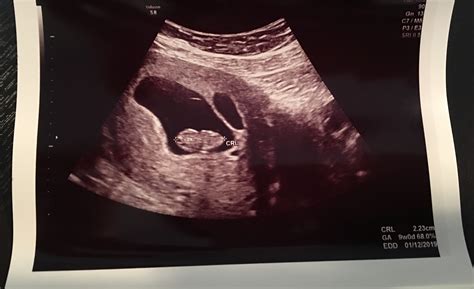

• Visualization of Embryos: At 7 weeks, the embryos are about the size of a blueberry. The ultrasound will show the gestational sacs, yolk sacs, and the fetal poles, which are the early forms of the embryos.

• Heartbeat Detection: In some cases, the fetal heartbeats may be visible, although it is not always detectable at this stage. The presence of a heartbeat is a positive sign of a viable pregnancy.

• Gestational Sacs: The presence of gestational sacs confirms the implantation of the embryos in the uterus.

• Yolk Sacs: Yolk sacs are essential for the early development of the embryos and should be visible at this stage.

• Fetal Poles: Fetal poles are the early forms of the embryos and should be visible within the gestational sacs.

• Heartbeats: The detection of fetal heartbeats is a positive sign of a viable pregnancy, although it may not always be visible at 7 weeks.